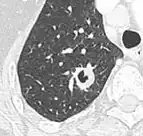

Lung nodule abutting a pulmonary cyst.[9]

• A lung nodule abutting a pulmonary cyst is a rare finding, yet indicating cancer.[9]